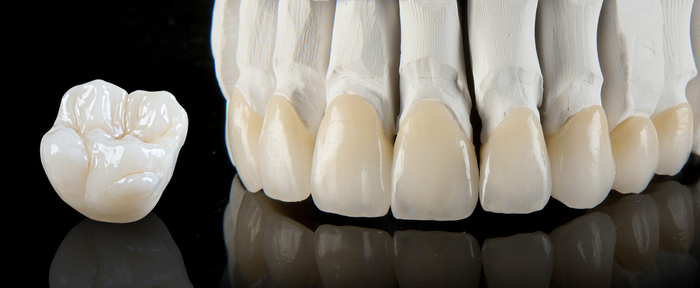

2 . Временная коронка лабораторная (длительного ношения, временная фрезерованная или коронка PMMA(полиметилметакрилат)\PEEK(полиэфирэтилкетон))

Изготавливается уже в зуботехнической лаборатории на фрезерном станке.

Плюсы:

-дешевая по сравнению с постоянными

-эстетичная, её можно подкрашивать

-прочная, можно носить до 1 года или даже больше

-можно всячески её корректировать

-можно нагружать сомнительные зубы, экономя деньги пациента

-легко снимать и одевать обратно

Минусы:

-стоит дешево, но не прям таки

-требуется слепок\скан и время на изготовлении в лаборатории

-хоть можно носить и долго, но всё равно износ у неё больше, чем у постоянных

-срок службы и прочность неплохие, но всё равно меньше, чем у постоянных

-как и любая временная, хуже держится даже на постоянных цементах.

Эта коронка идеальная, когда надо закрыть зуб на длительное время, чтобы потом в случае чего вернуться к лечению. Например, при лечении кист на разрушенных зубах. При таком лечении никто не может дать гарантию, что зуб получится спасти. Сперва его наблюдают на сроках до 1 года. Всё это время зуб должен функционировать должным образом, поэтому его перекрывают коронкой. Ставить в таких случаях постоянную коронку не всегда гуманно по отношению к кошельку пациента, так как зуб в итоге может пойти под удаление. Тут как раз она будет идеальным решением, так как стоит в несколько раз дешевле.

Также эту корону используют при исправлении прикуса и лечении сустава, так как она легко корректируется во всех смыслах. Её можно не только подпиливать, но и добавлять материал прямо в кресле врача. Подобной коронкой можно и моделировать контур десны, в том числе и вокруг имплантов.

К тому же её тупо можно использовать, когда нужна позарез коронка, но финансовая яма не позволяет сделать что-то основательное.